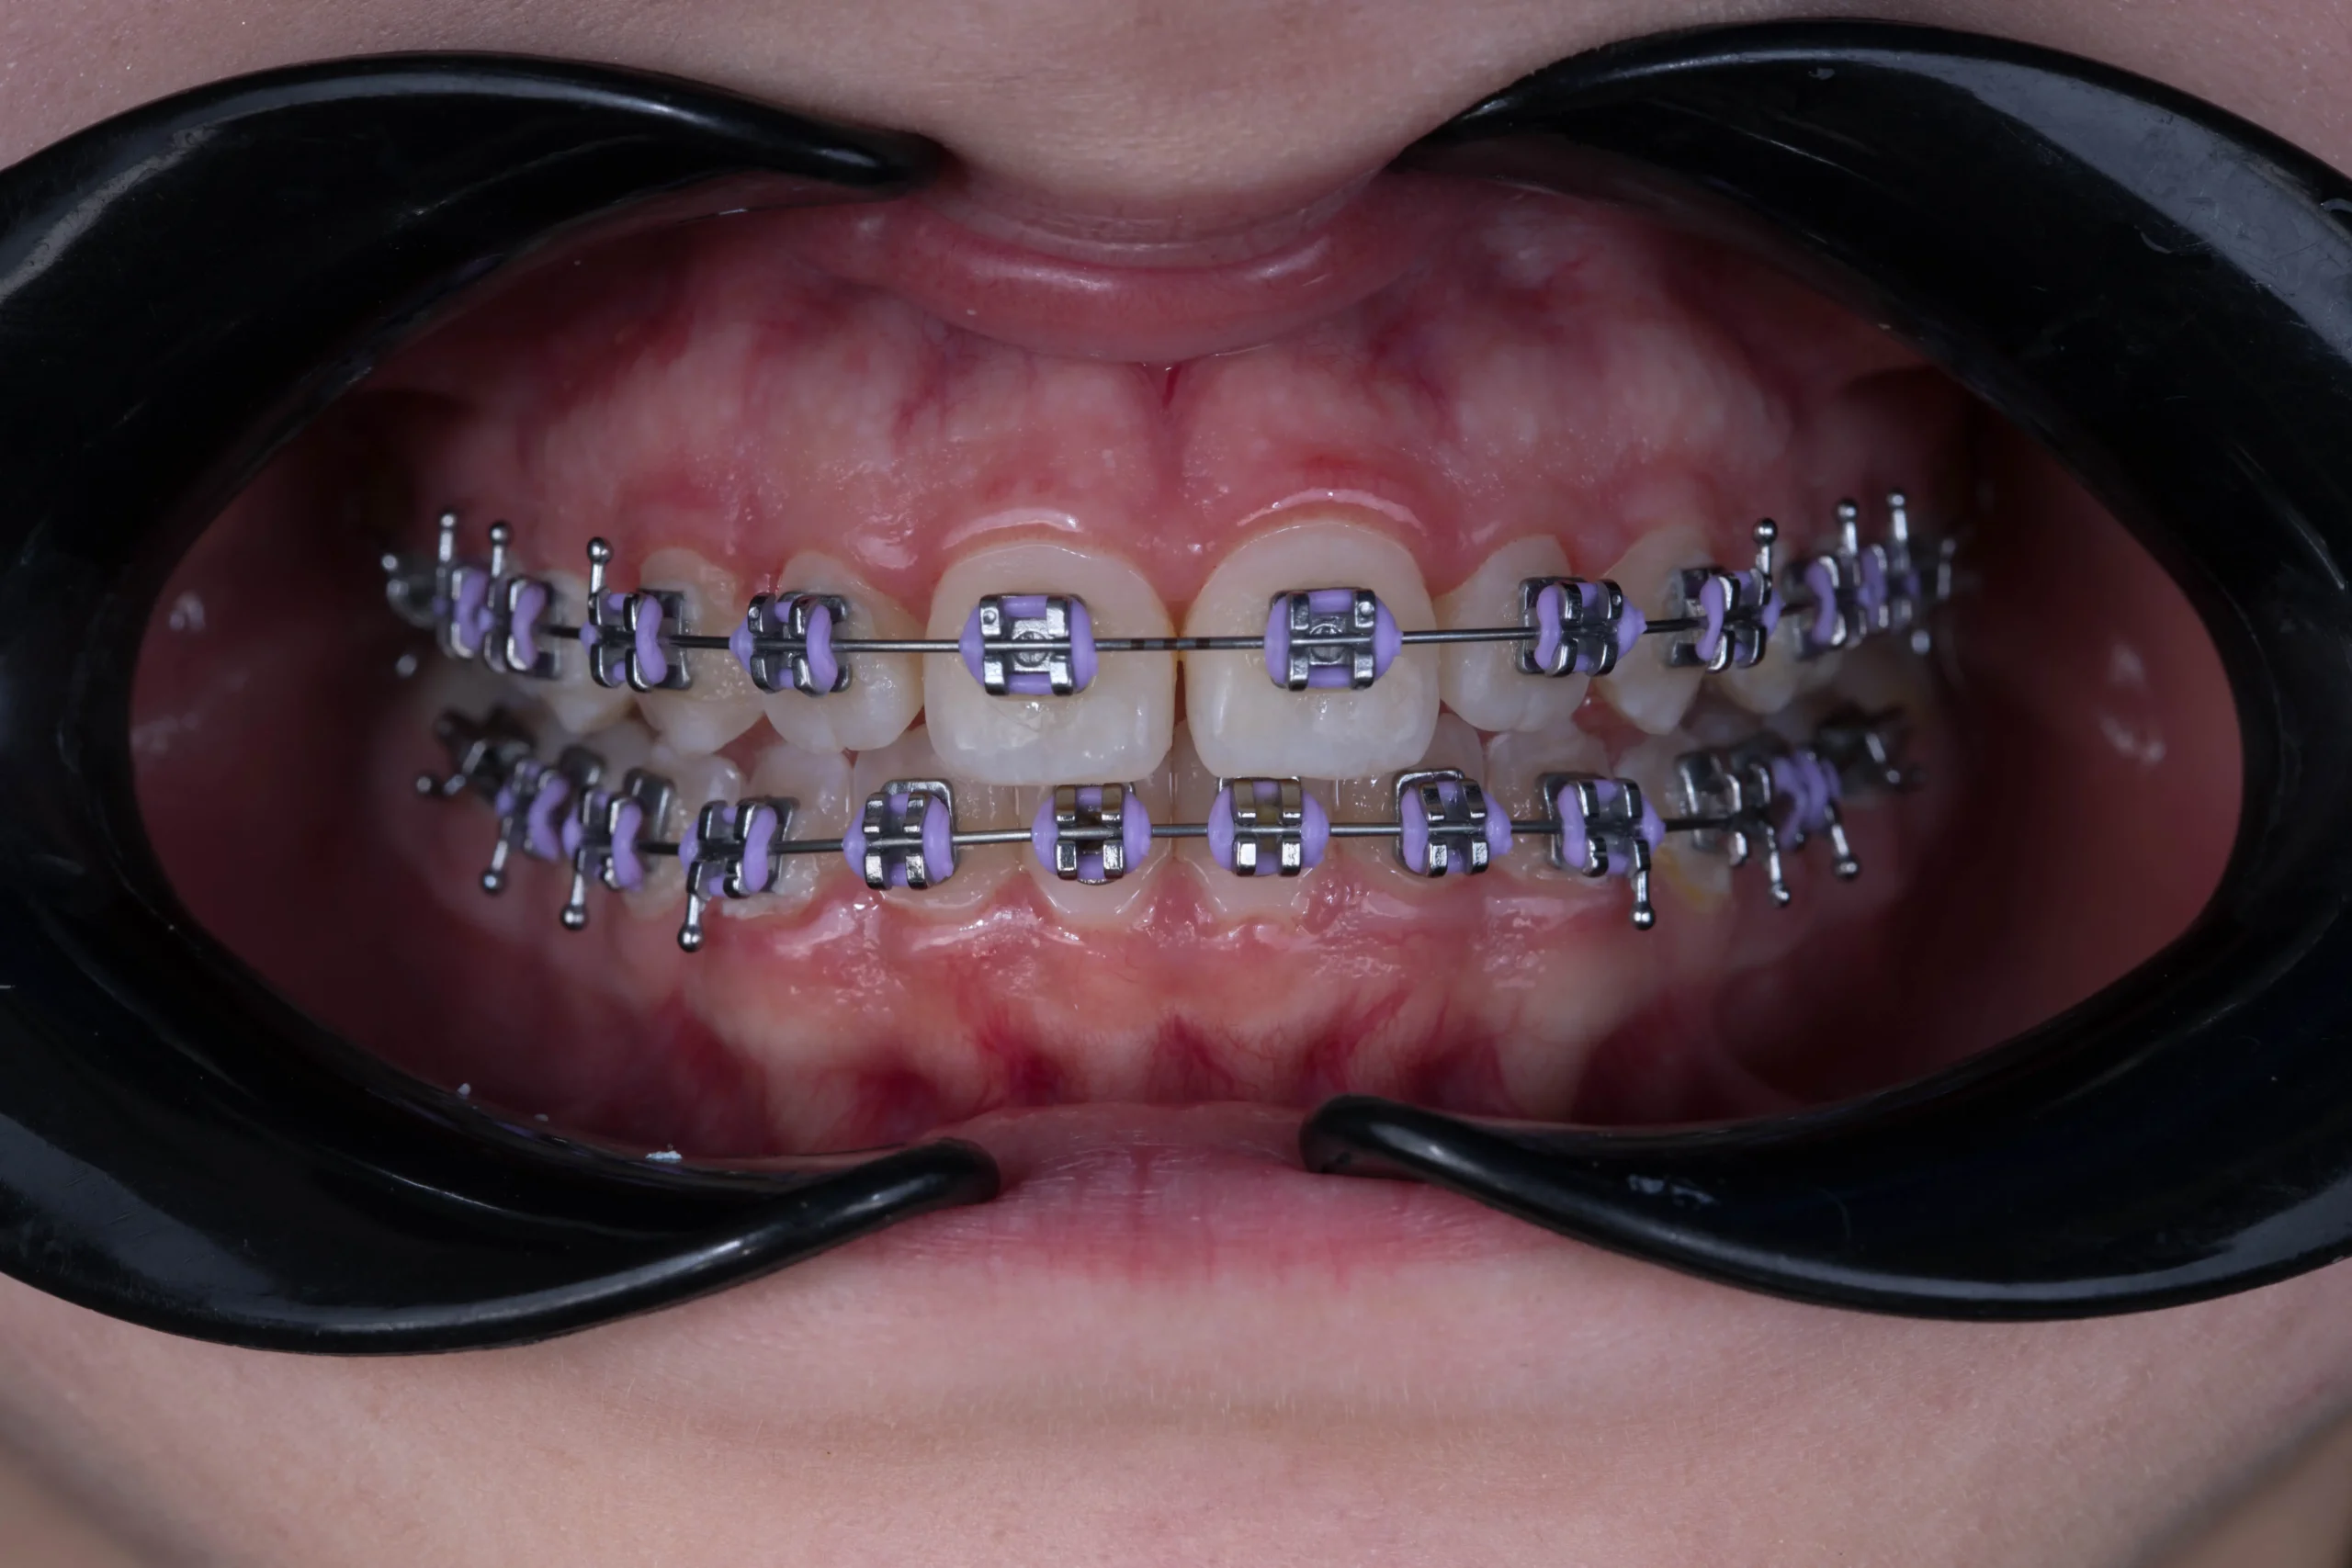

Ortodoncia

Ortodoncia en Bucaramanga recupera tus dientes con resultados naturales.

Soluciones de ortodoncia personalizadas: brackets tradicionales, sistemas estéticos y alineadores invisibles.

Tipos / sistemas que ofrecemos

- Ortodoncia convencional (brackets metálicos).

- Brackets autoligados (mayor comodidad y menor fricción).

- Brackets de zafiro (estéticos/translúcidos).

- Flow Jack (mini tubos / sistema discreto).

- Alineadores transparentes (removibles y estéticos).

¿Qué es la ortodoncia?

Especialidad que corrige la posición de los dientes y las relaciones entre los maxilares para mejorar la función masticatoria, la estética facial y la salud a largo plazo.